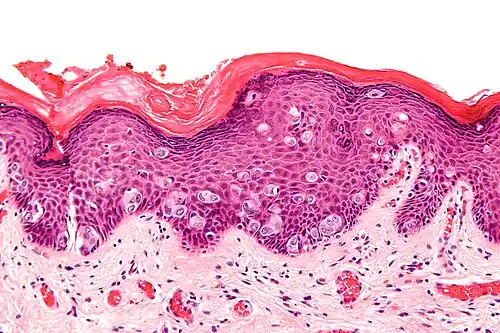

| Micrograph of extramammary Paget's disease, H&E stain | |

It is important to include that the lesion is associated with another cancer. A biopsy will establish the diagnosis. Punch biopsies are not effective in differentially diagnosing for EMPD and as a result, excisional biopsies of the affected area are taken [XX]. A positive test result for EMPD shows increased numbers of large polygonal cells with a pale bluish cytoplasm, large nucleus and nucleolus, infiltrating the epidermal layer.[7] These neoplastic cells can be found singly scattered or can appear in groups called nests.[7]